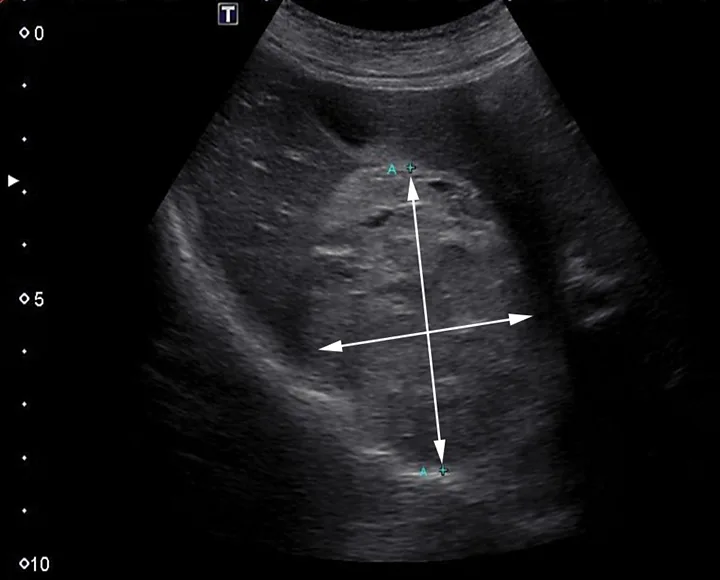

Histopathology of hepatic mass with compressed hepatocytes (star) and splenic red pulp (diamond). Necrosis can be seen in the lower left corner.

Although neoplasia was suspected, it could not be confirmed without histopathology. The owners elected for abdominal exploratory surgery to attempt either complete mass resection or debulking with biopsy for histopathology. The owners were prepared to consult with the oncology team following surgery if neoplasia was confirmed. Three liver masses and one mass adhered to the linea alba with omental adhesions were removed, leaving smaller masses and irregularities throughout the liver. The largest mass (11 cm), located in the left medial liver lobe, was firm and vascular and interspersed with pockets of unclotted blood. The left medial liver lobe containing the largest liver mass, 2 additional liver masses, and a mass adhered to the linea alba with omental adhesions were all removed, leaving smaller masses and irregularities throughout the liver. On histopathologic examination, the hepatic masses were found to be composed of red pulp, extramedullary hematopoietic tissue, rare white pulp, and smooth muscle trabeculae (Figure 3). The mass associated with the linea alba was also composed of ectopic splenic tissue, with similar components, consistent with splenosis. No evidence of neoplasia was seen. Recovery was uneventful, and the patient was discharged 2 days postoperatively.